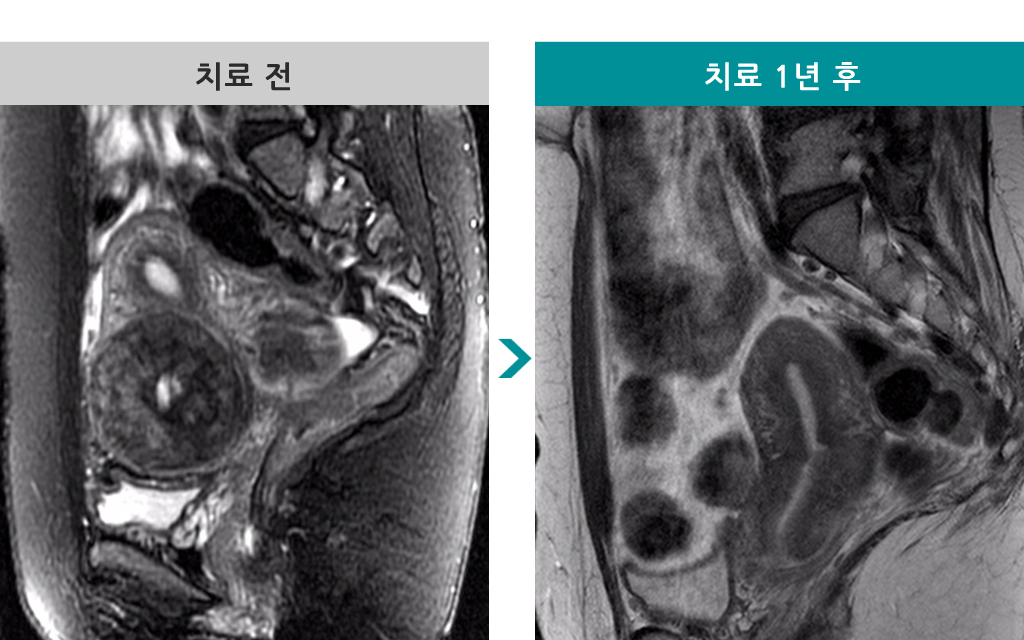

38세 [자궁근종 색전술] 전후 MRI사진 비교